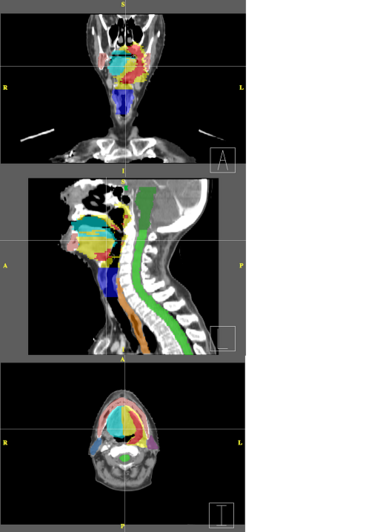

Below are examples of segmentations of targets and critical structures for head and neck, and thorax. These structures (or similar) would be manually delineated for every patient who gets 3D planning.

|